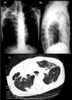

Pleuropulmonary fibrosis at lung apex